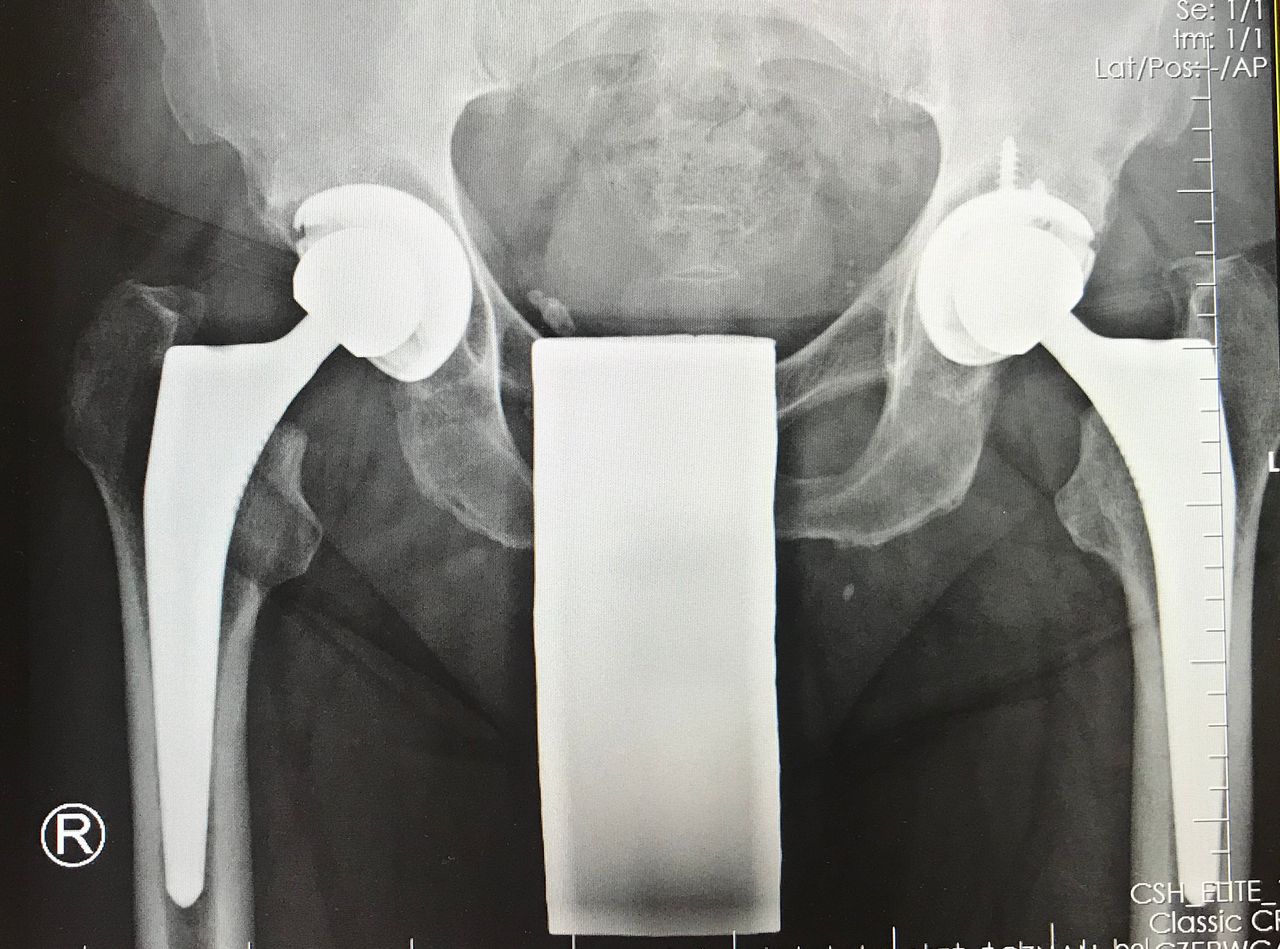

endoprotezoplastyka stawu biodrowego (dostęp małoinwazyjny DSA)

Endoproteza stawu biodrowego